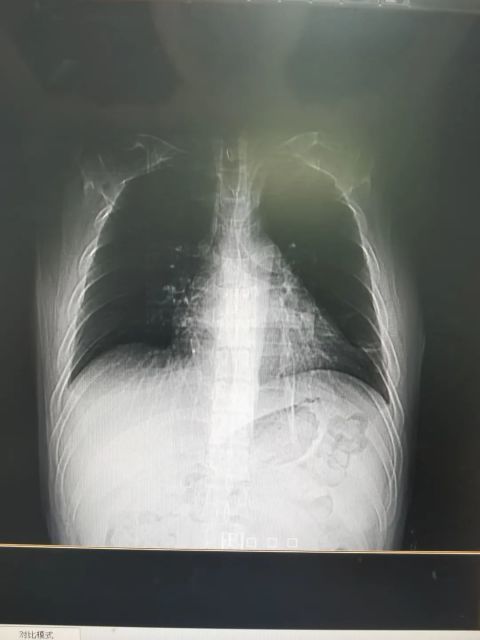

文章插图

治疗后胸片:渗出灶全部吸收 糖尿病呈年轻化 , 这些症状要及时就医